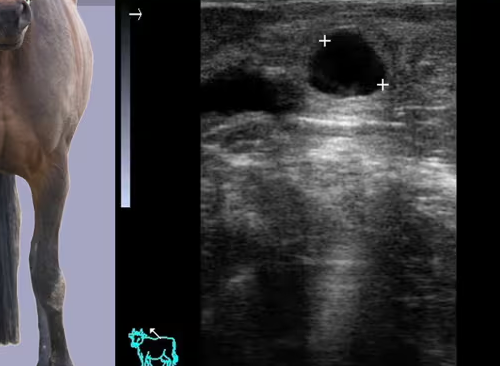

Wie führt man eine geburtshilfliche Berechnung für Tiere durch? Das Instrument ermöglicht Messungen des Gestationsalters von Tieren wie Pferden, Rindern usw.